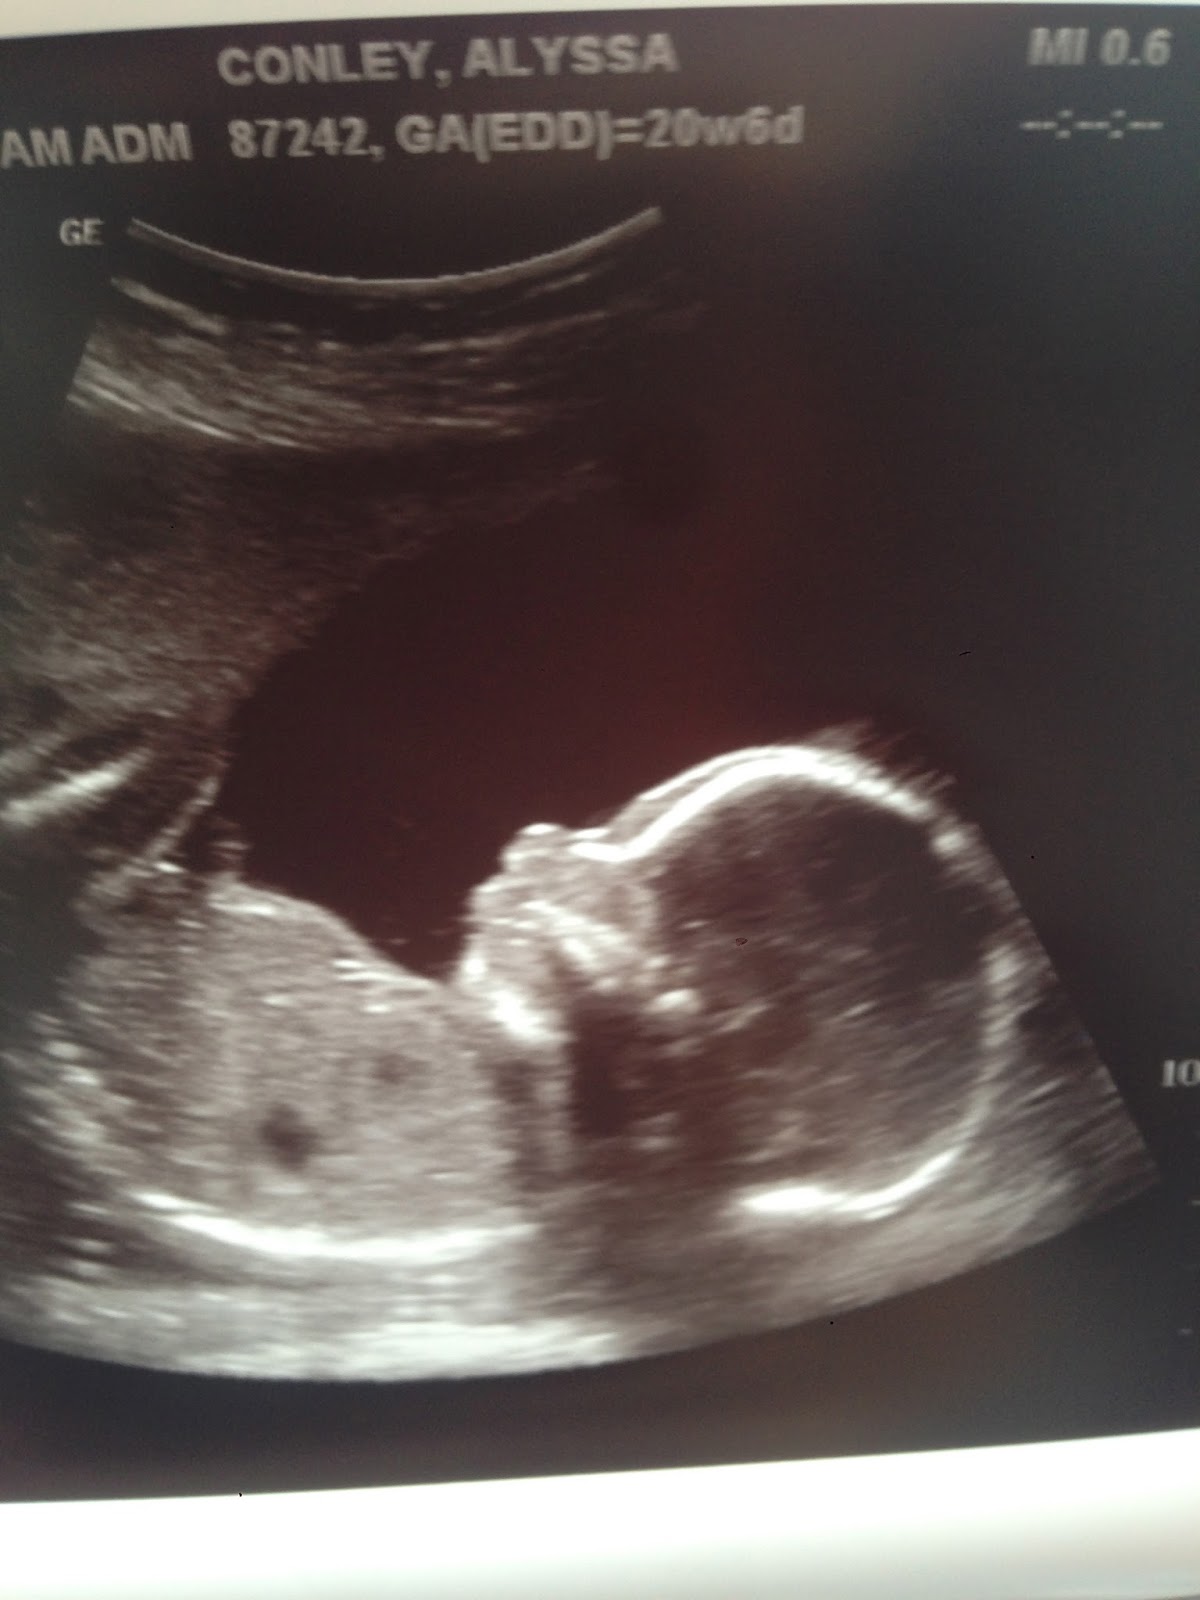

Finally got this stinker to lift his chin to get a good profile picture. Love this little guy :)